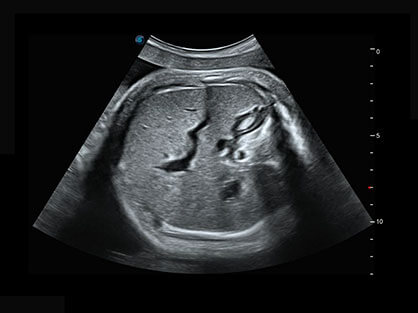

作为P系列家族成员之一,P40 Plus采用百老汇电子游戏官网高端超声系统平台——极光,并以时尚秀丽、小巧灵动的外观设计绽放出灵动之韵、科技之美。高端平台的使用保证了P40 Plus优质的基础图像;完备的高级功能可满足您全身应用的基本需求;丰富的探头配置、多样的高级4D成像及分析软件为您日益增多的妇产应用需求提供丰富的诊疗方案。

结合百老汇电子游戏官网超宽频带探头技术优势,能够更好地获得高分辨力与高穿透力的平衡,保证图像质量,为临床诊断保驾护航。

微米成像技术提升了对组织斑点噪声信号的抑制能力,并进一步强化边界信息,从而获得清晰图像。